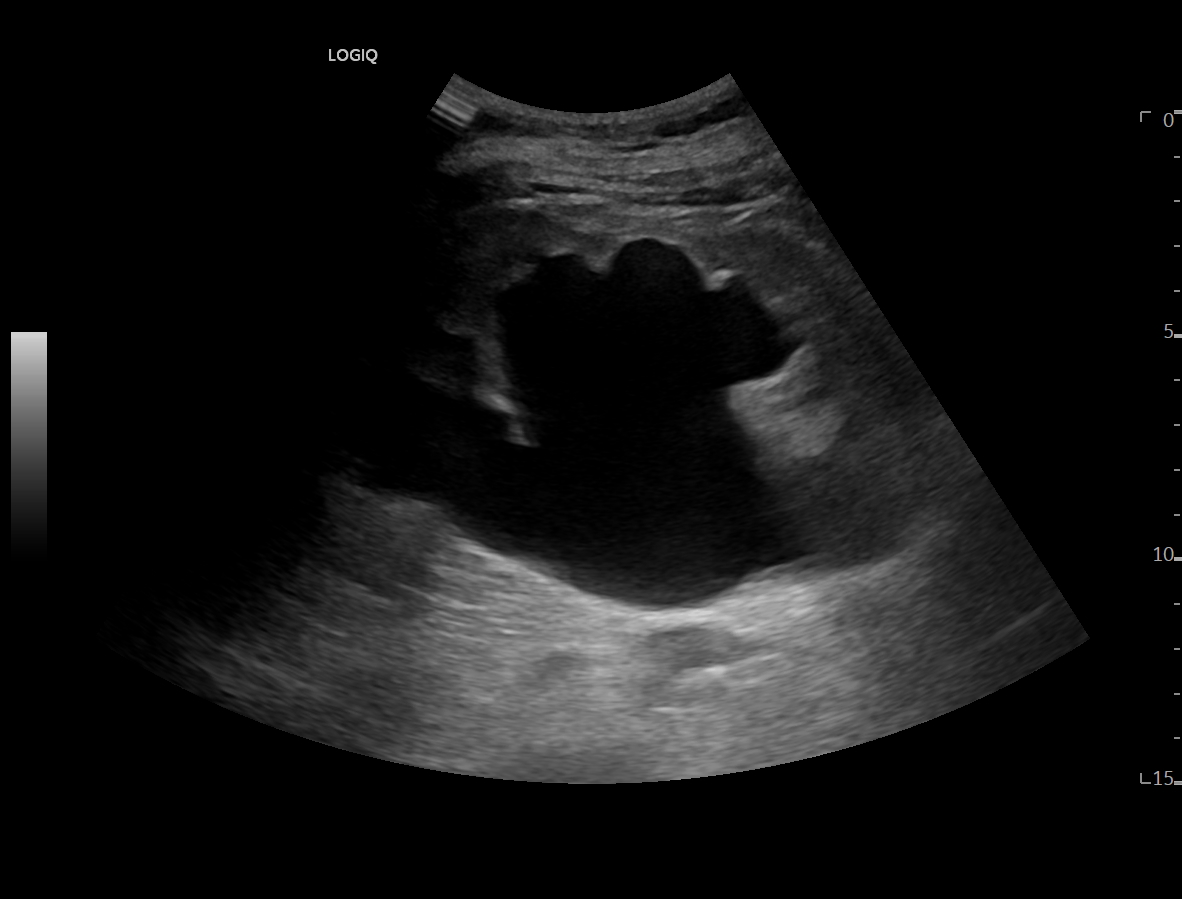

Ya en urgencias hospitalarias, se realiza ecografía clínica donde se aprecia ureterohidronefrosis derecha grado IV con pérdida completa de ecoestructura renal por el incremento del volumen que presenta, no presentando las mismas alteraciones en el lado izquierdo, pudiendo esto indicar una obstrucción completa no resuelta.

La ecografía clínica reglada informa de dilatación de pelvis renal de hasta 5,7 cm con aumento de tamaño renal hasta 13 cm, apreciando litiasis obstructiva de 12 mm en uréter distal a unos 5 cm del meato ureteral derecho.